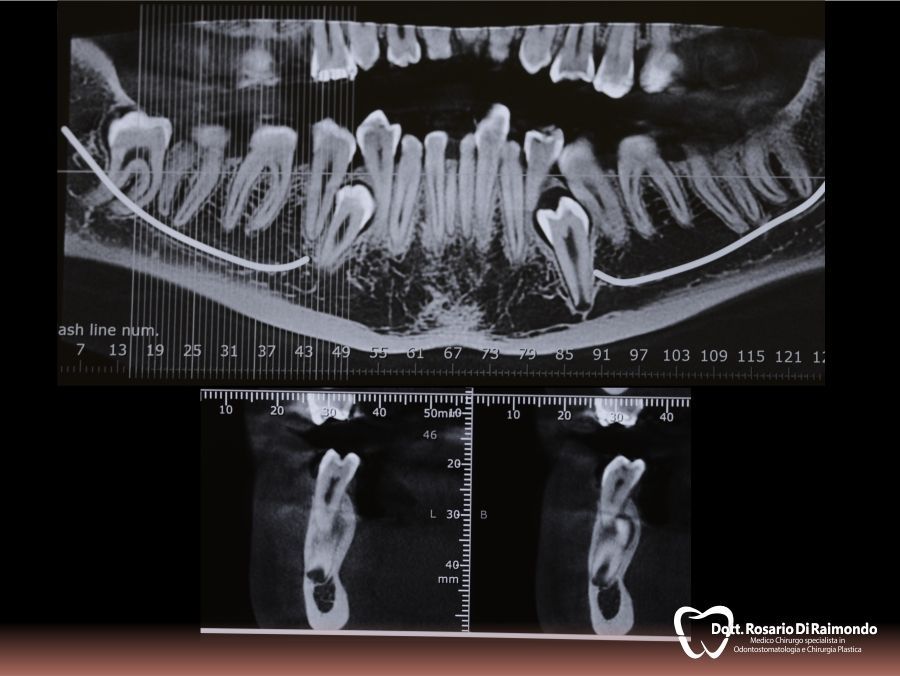

Casi Trattati

Di seguito riportiamo alcune fotografie di casi esplicativi di Chirurgia Orale.